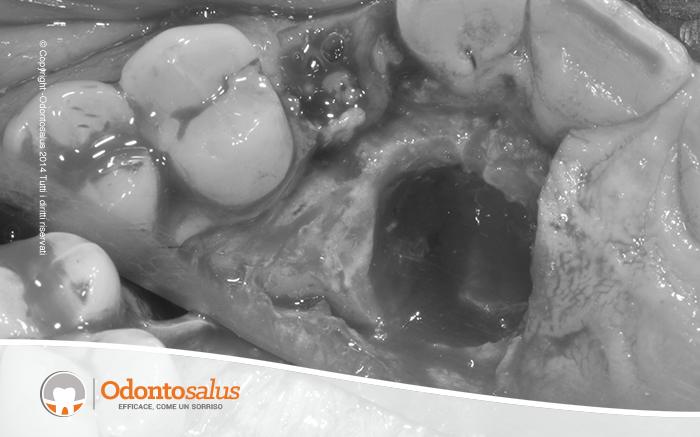

Inizialmente è stato effettutao un trattamento ortodontico per riportare l’elemento incluso in arcata. Tuttavia, come a volte accade in relazione all’età del paziente, alla densità ossea o alla posizione del dente incluso, ortodonticamente non è stato possibile riallineare il canino con gli altri denti. Si è proceduto, pertanto, con l’incisione del lembo, la scopertura e l’estrazione del canino, il riempimento del deficit osseo creato, l’applicazione dell’impianto e, data la sua stabilità, l’inserimento del provvisorio nella stessa seduta.